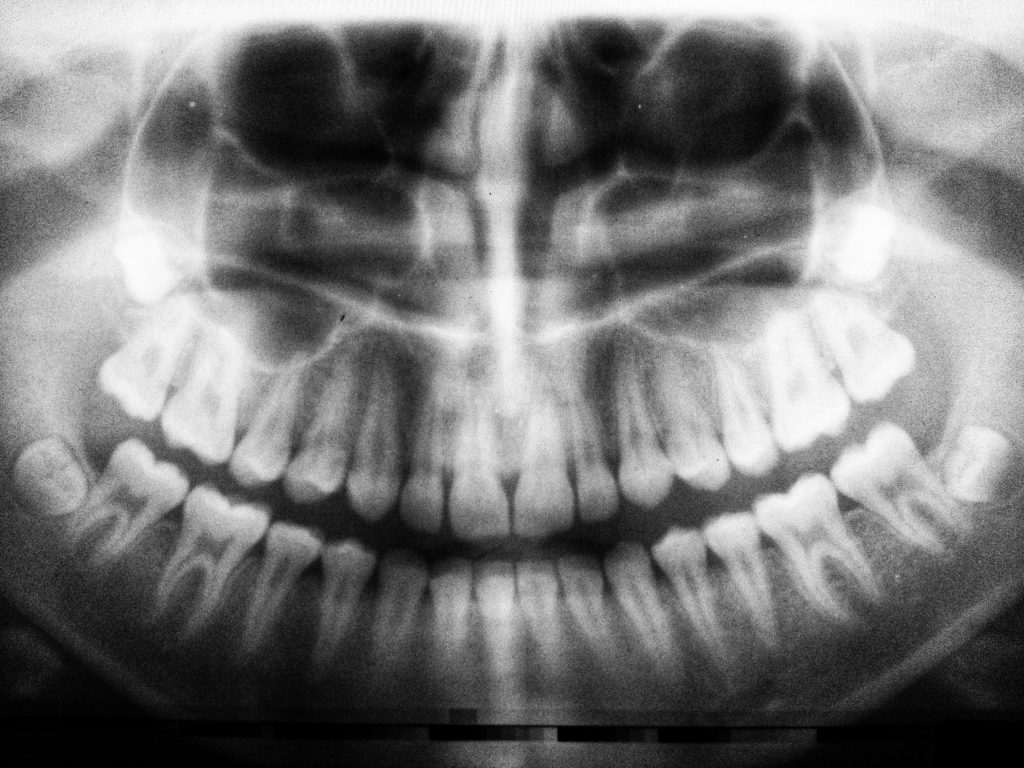

- esami radiografici mirati quando indicati

La prima visita odontoiatrica comprende la raccolta dell’anamnesi generale, l’esame clinico dei denti e dei tessuti gengivali, la valutazione della funzione masticatoria e, quando necessario, esami radiografici mirati.